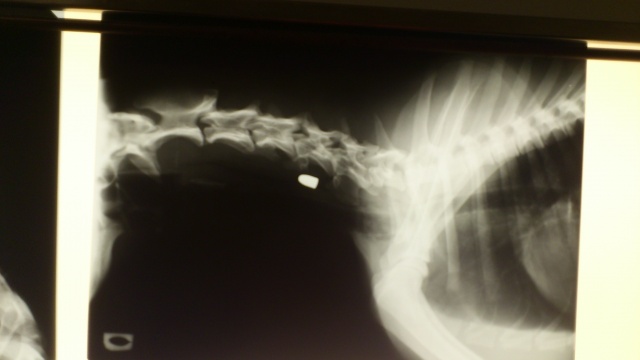

Läbivaatusel selgus, koera on tulistatud näkku. Röntgen näitas, et kuul on läbinud ülemise koonuosa ja keele ja jäi kõrisse pidama. Loodame, et kõik läheb hästi ja koer paraneb kiiresti.

Собаку нашла женщина, которая испугалась, что собака попала под машину: на цепь наехало колесо машины. Собака поступила к нам и при ближайшем рассмотрении выяснилось, что собаке стреляли в лицо из 9мм оружия. Сделали рентген, определили местонахождение пули.